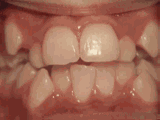

前牙移位,因为有牙齿缺失,导致相邻牙齿开始没有秩序的前突,经过矫正后是变成这样的~